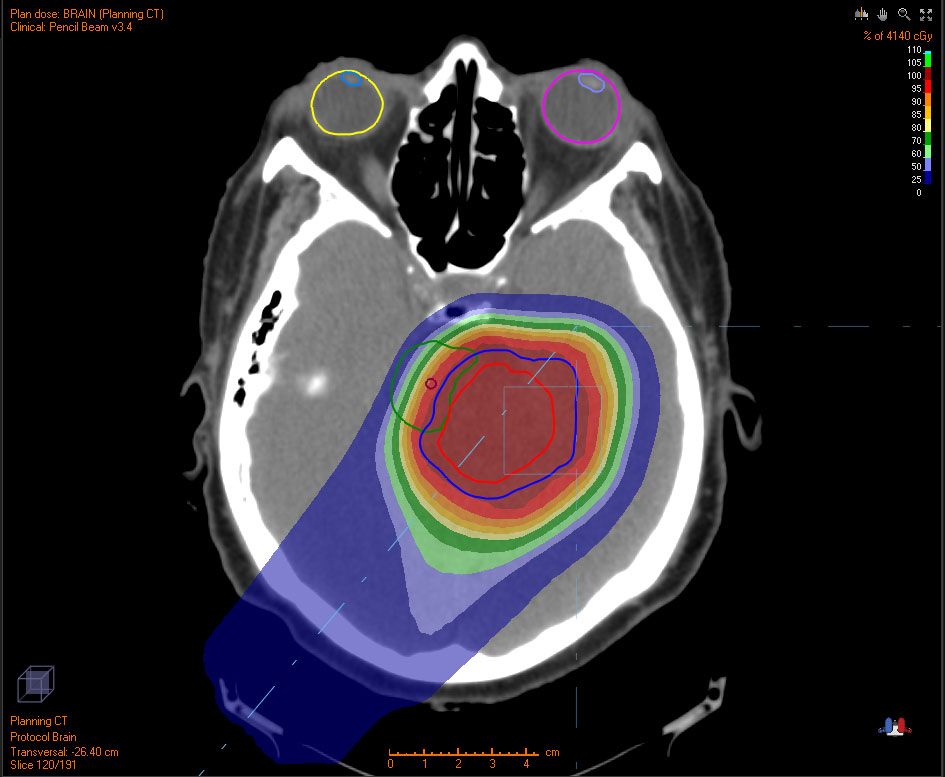

The slight risk of developing cancer from radiation therapy is lower for proton than conventional x ray photon treatment. The areas marked red received a higher dose while the fields in blue and violet received low dosages. Discover our proton therapy solutions and many more health care products and services.

Find the perfect proton therapy stock photo. X ray therapy left and proton therapy right the above images show tissue exposed to conventional radiation therapy left image and proton therapy right image by the application of intensity modulated treatment. Proton therapy is a type of external beam radiotherapy that uses ionizing radiation.